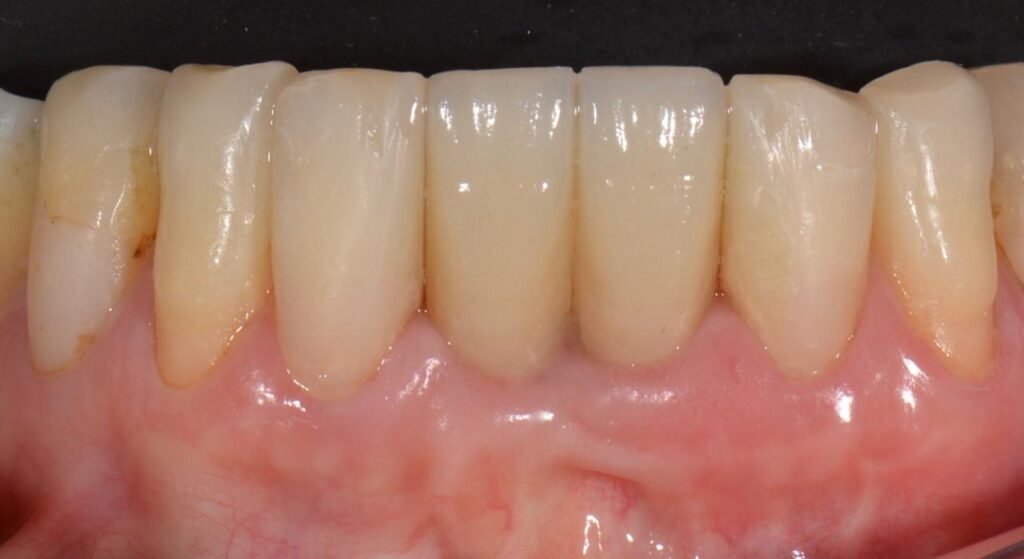

Utilizando as técnicas de acordo com classificação proposta, é possível construir um parede vestibular que se mantém íntegra ao longo do tempo, mantendo a estética dos casos e tornando os implantes imediatos uma alternativa segura independente da situação da tábua óssea vestibular do alvéolo.